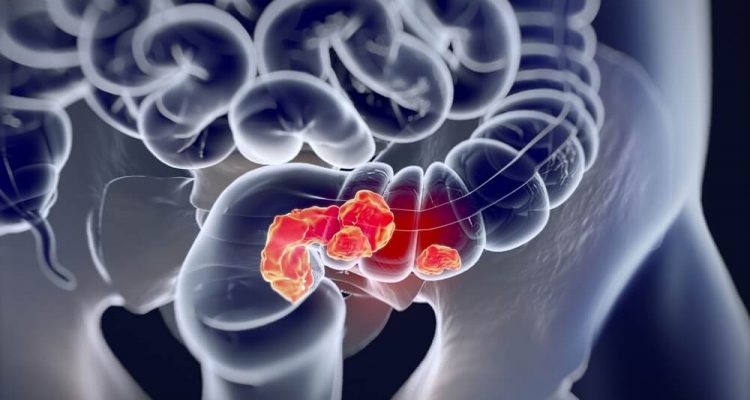

“Нирки людей більше не справляються повністю із завданням фільтрацією шкідливих речовин з крові і виведенням їх через сечу. У кожного десятого порушена функція нирок”, – говорить Клеменс Коен.

Лікарка попереджає: нирки довго страждають тихо і не болять (виняток становлять тільки камені в нирках). Ниркова дисфункція може виражатися в загальних симптомах, коли людині може вже вимагатися діаліз. Згідно з дослідженням, хронічна ниркова недостатність в останні роки збільшилася в статистиці більше, ніж будь-яка інша хвороба.

“Малорухливий спосіб життя з продуктами, які забезпечують багато калорій, в поєднанні з відсутністю фізичних вправ, завдає шкоди ниркам через високий кров’яний тиск і діабет. Крім того, деякі інгредієнти можуть безпосередньо обтяжувати наші нирки. Це особливо вірно, коли функція нирок вже порушена», – повідомила експертка.